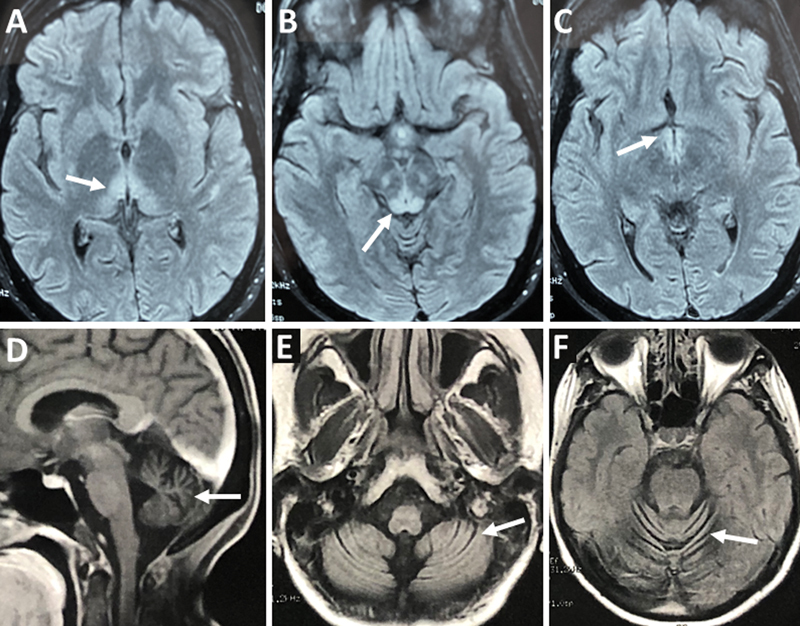

The rates of complications after major abdominal surgeries remain high, despite the advances in pre- and postoperative care and surgical techniques. In these cases, neurological disorders mainly include stroke and delirium, with a high increase of morbidity. Ataxia is rarely a consequence of abdominal procedures like, more often being related to long-term complications of bariatric surgery due to chronic vitamin deficiency.To describe seven cases of ataxia following major abdominal surgeries and propose a prophylactic approach.A retrospective case series in which medical records of patients from the Ataxia Unit of Universidade Federal de São Paulo were evaluated from January 2007 to August 2024. We identified seven patients who developed acute cerebellar ataxia after gastrointestinal surgery. Demographic, clinical, laboratory, neuroimaging, and treatment data were extracted. Descriptive statistics was used to summarize findings.There were two cases that evolved with neurological improvement, and five remained with severe cerebellar ataxia. Brain imaging showed cerebellar atrophy in three patients and signs of Wernicke encephalopathy in two.This case series describes an unusual form of acute ataxia with poor outcomes, possibly related to complications from major abdominal surgery. Early intervention and prophylactic supplementation with vitamins B1 and B12 in patients receiving TPN should be considered to avoid such severe neurological complications.